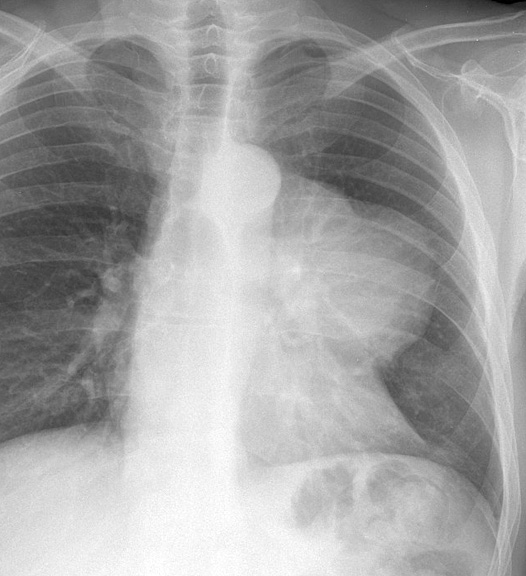

Case 7a

Malig Thymoma